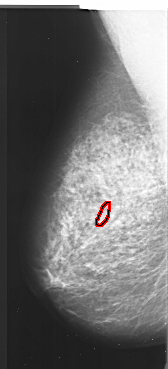

A_1026_1.LEFT_CC

LEFT_CC LINES 6211 PIXELS_PER_LINE 2866 BITS_PER_PIXEL 16 RESOLUTION 42 OVERLAY

FILE: A_1026_1.LEFT_CC.OVERLAY

TOTAL_ABNORMALITIES 1

ABNORMALITY 1

LESION_TYPE CALCIFICATION TYPE PLEOMORPHIC DISTRIBUTION CLUSTERED

ASSESSMENT 4

SUBTLETY 1

PATHOLOGY MALIGNANT

TOTAL_OUTLINES 1